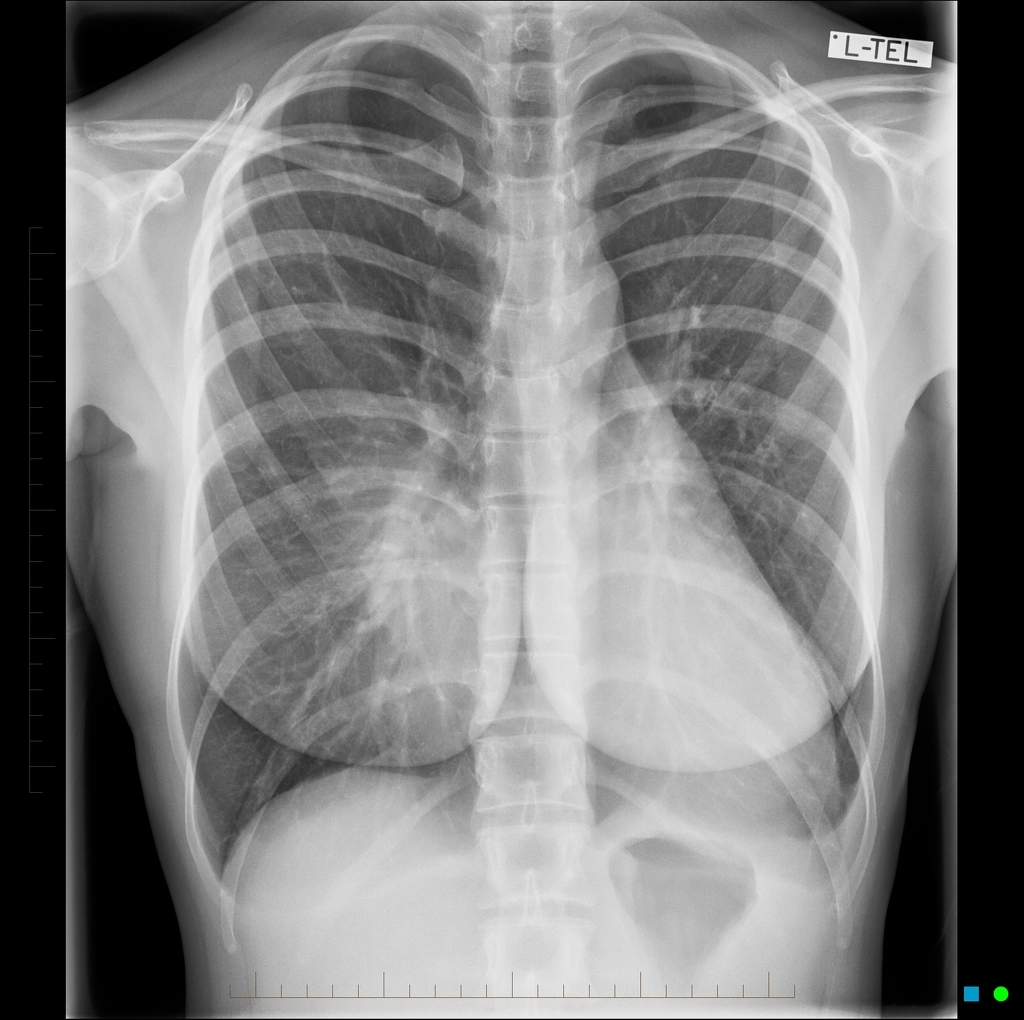

25 ANOS, RAIO-X PRÉ-OP

PECTUS EXCAVATUM